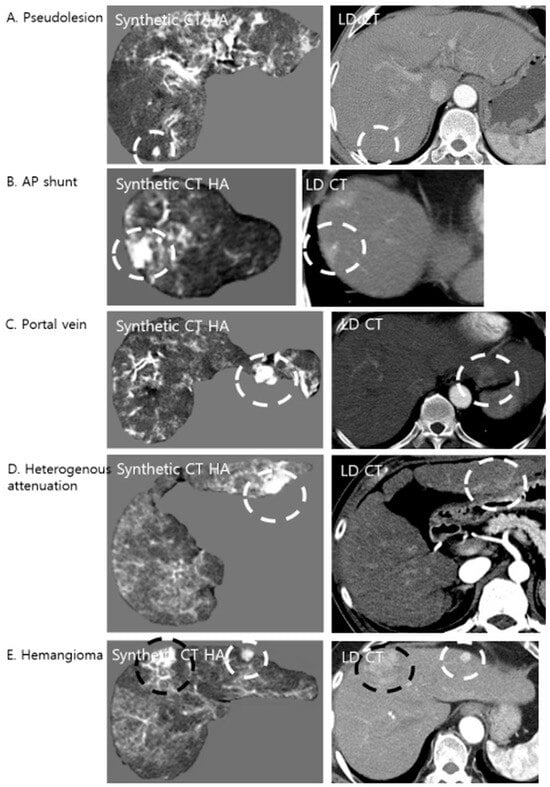

3.4.1. Etiology of False Positives

Retrospective analysis of the corresponding LDCT images revealed the primary cause of these false positives (Figure 4). The predominant etiology was an arterioportal (AP) shunt (n = 47), which accounted for the majority of cases. Since AP shunts exhibit early arterial enhancement, physiologically mimicking HCC, the model, which was trained to amplify hypervascular features, accentuated these regions, rendering them nodular in appearance. Other anatomical confounders included cross-sections of the hepatic vessels (n = 15), focal areas of heterogeneous liver parenchyma (n = 14), and flash-filling hemangiomas (n = 2), all of which presented high attenuation values that the algorithm interpreted as potential lesions.

Figure 4. Examples of false-positive lesions on Synthetic CTHA. The algorithm may enhance non-tumorous structures, mimicking hypervascular nodules. The white dashed circles indicate pseudolesions, while the black dashed circles indicate the confirmed hypervascular hepatocellular carcinoma (HCC) lesions. (A) A pseudolesion generated in the absence of any enhancing structure on LDCT. (B) An arterioportal (AP) shunt showing early enhancement is accentuated, appearing nodular. (C) A cross-section of a portal vein mimicking a nodule. (D) Focal heterogeneous liver attenuation amplified by the model. (E) A flash-filling hemangioma showing enhancement patterns similar to HCC on the synthetic image.